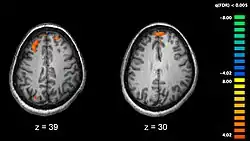

Schizofrenia este corelată cu diferențe subtile ale structurilor cerebrale, prezente în 40-50% din cazuri și de chimie cerebrală, în timpul stărilor psihotice acute.[8] Studii care folosesc teste neuropsihologice și tehnologii de obținere a imaginilor creierului, cum ar fi fMRI și PET pentru a examina diferențele de activitate cerebrală au arătat că diferențele care apar în mod obișnuit sunt în lobii frontali, hippocampus și lobii temporali.[68] Reduceri ale volumului creierului, mai mici decât cele observate în cazul bolii lui Alzheimer au fost raportate în zonele cortexului frontal și lobilor temporali. Este însă nesigur dacă aceste schimbări de volum sunt treptate sau preexistente apariției bolii.[69] Aceste diferențe au fost asociate cu deficiențe neurocognitive care sunt corelate schizofreniei.[70] Deoarece circuitele neurale sunt afectate, s-a sugerat alternativa că schizofrenia trebuie gândită drept o asociere de tulburări de dezvoltare neurologică.[71]

- ↑ Kircher, Tilo and Renate Thienel. The Boundaries of Consciousness. Amsterdam: Elsevier; 2006. ISBN 0444528768. Functional brain imaging of symptoms and cognition in schizophrenia. p. 302.